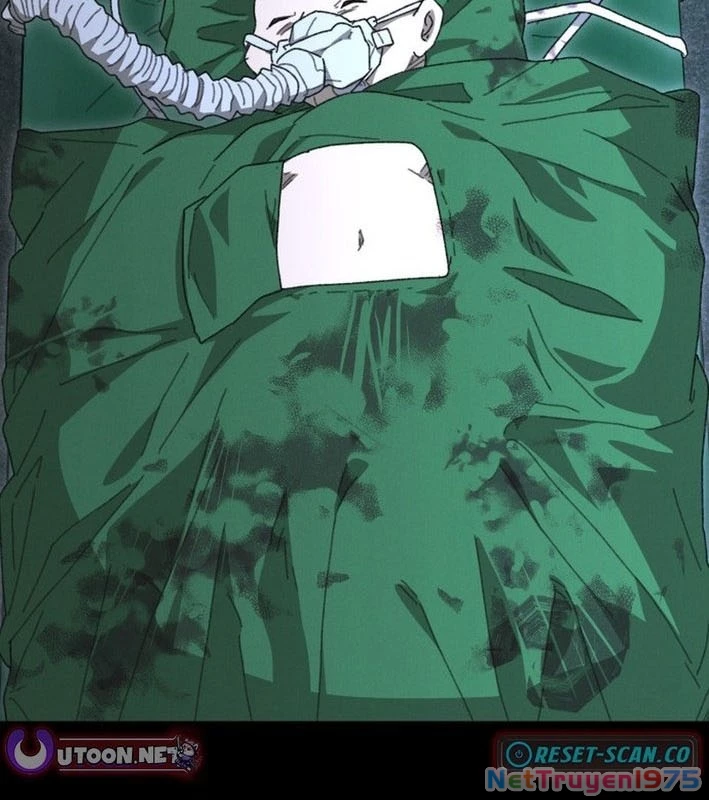

Kẻ Chôn Cất Quái Vật - Chapter 1